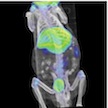

We offer nuclear, x-ray, and optical imaging solutions utilizing dual-modality microPET/CT and microSPECT/CT, and bioluminescence/fluoresence imaging systems. Our housing facility is managed by LARC and is classified as an “in-and-out” facility that is well suited for longitudinal studies. Our imaging scanners are run by highly trained professionals. We also have imaging science experts to provide additional help on image reconstruction, co-registration, tracer kinetic modeling, and quantifications.

- Whole-body rodent PET, SPECT, CT, bioluminescence, fluorescence

- Dual-modality PET and SPECT combined with CT